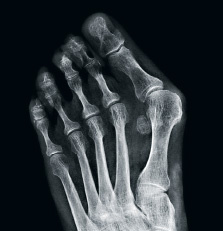

Die Untersuchung beginnt mit einer Begutachtung der Schuhe, der Inspektion der Füsse und der Analyse des Gangbilds von Anna Schwegler. Speziell darauf zu achten ist, ob Schwielenbildungen oder auf Druck auslösbare Beschwerden bestehen. Anschliessend folgen Tests auf Beweglichkeit der einzelnen Gelenke, Nervenempfindungsstörungen, Durchblutungssitua­tion und die Stabilität der Gelenke. Von zentraler Bedeutung ist das Röntgenbild. Es muss zwingend im Stehen angefertigt werden, um die Statik der Gelenke zueinander unter Belastung beurteilen zu können.

Je nach Ursache, die gefunden wurde, gibt es mehrere operative Möglichkeiten, um die Beschwerden der Patientin zu beheben. Sind die Beschwerden auf einen Hallux valgus zurückzuführen, so sollte dieser operiert werden, um die Fehlbelastung des Fusses zu korrigieren. Bei einem zu langen Mittelfussknochen muss dieser operativ verkürzt werden. Sind Hammer- oder Krallenzehen die Ursache für die Beschwerden, so kann der Spezialist diese mit gut etablierten operativen Eingriffen begradigen.

Metatarsalgien können oft auf einen Hallux valgus (hier vor und nach der Operation) zurückgeführt werden.

Bei Anna Schwegler ist die Ursache für ihre Schmerzen eine Hammerzehe mit einem zu langen zweiten Mittelfussknochen. Früher wurde bei dieser Diagnose ein Draht durch die Zehe gebohrt, der vorne herausschaute. Das hielt viele Patienten von einem Eingriff ab. Anna Schwegler hat sich zusammen mit dem Spezialisten für ein neues Operationsverfahren ent­schieden, bei dem die Schienung nicht aus einem Draht, sondern aus selbstauflösenden Zuckerstiften besteht. Damit wurden im Salem-Spital in jüngster Vergangenheit sehr gute Erfahrungen gemacht.